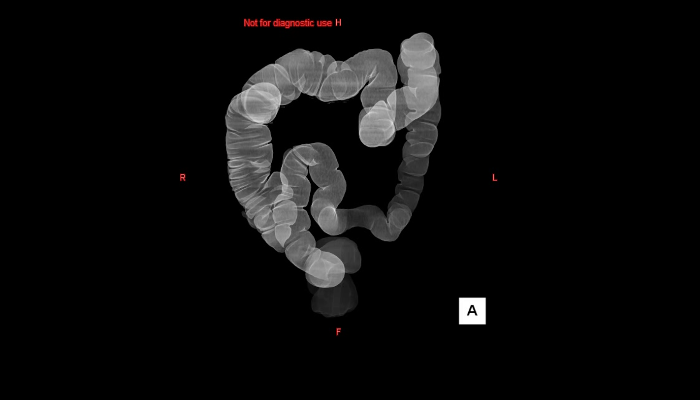

大腸CT検査について  ABOUT  CT COLONOGRAPHY

大腸CTとは、内視鏡を使用せずに大腸を観察する検査です。大腸を炭酸ガス(空気に比べて約130倍の速度で大腸に吸収されるので、腹部膨満感が軽減します)を用いて拡張させた状態で撮影することで、大腸の3D画像を作成します。大腸CT検査ではいくつか注意事項があります。場合によっては検査が行えないこともありますので、よくお読み頂き、ご不明な点はお尋ねください。

大腸CTのメリット

• 体外からの撮影のため苦痛が少なく、約10分と短時間で終了します

• 内視鏡の挿入が困難なケースにも対応可能です

• 3Dで観察ができるため、全体を評価でき、内視鏡の死角がありません